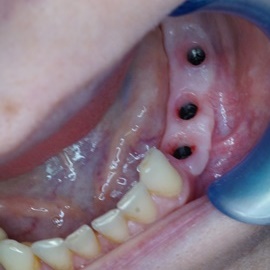

Implantacja natychmiastowa. Zęby paradontyczne. Usuniete zgodnie z popularną obecnie na zachodzie techniką: usuń zęby zanim zaniknie kość. Wynikiem takiego postępowania jest mniejsza trauma dla pacjenta i krótszy okres trwania rehabilitacji protetycznej, niższe całkowite koszty leczenia. Ale jednocześnie więcej implantów i mniej własnych zębów. W długotrwałym okresie obserwacji takie podejście daje dobre wyniki.